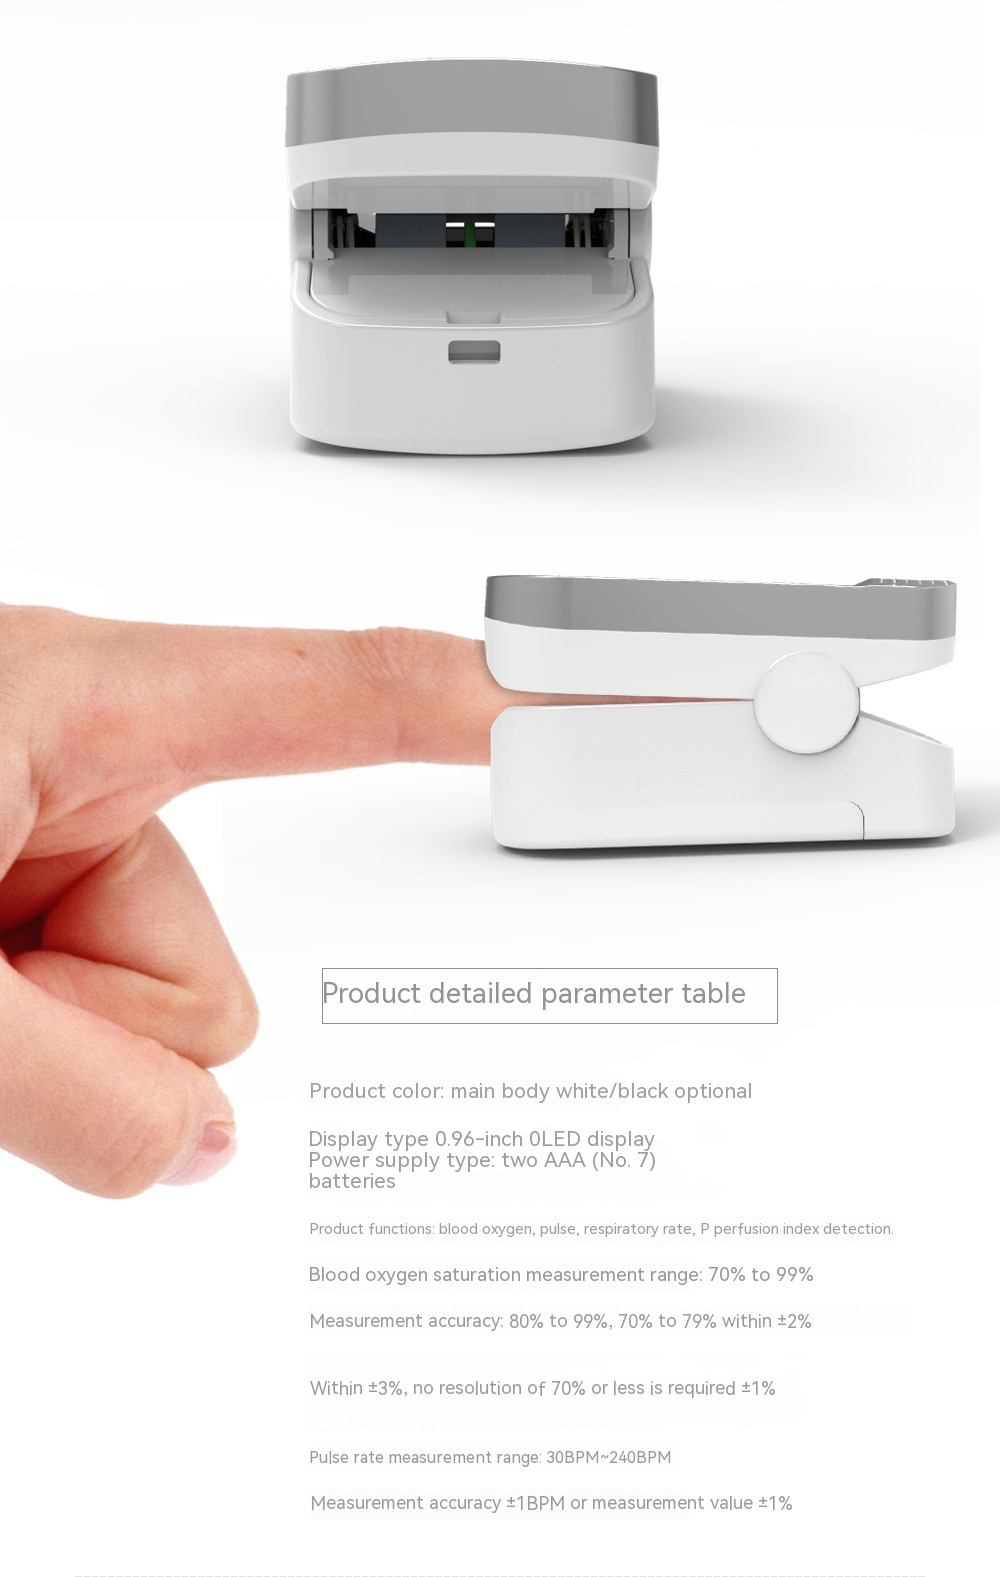

Product Image: